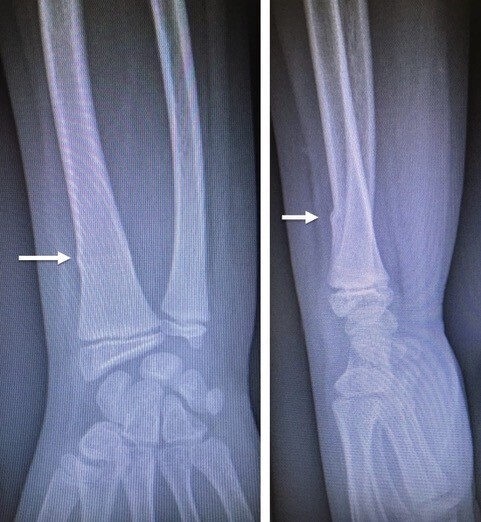

La lésion de Monteggia associe une fracture de l’ulna et une luxation de la tête radiale. Il faut se souvenir que « toute fracture isolée de l’ulna doit faire rechercher une luxation associée de la tête radiale ». L’axe du radius, quelle que soit l’incidence, doit couper le centre du condyle latéral de l’humérus. En cas de luxation de la tête radiale, cette ligne (ligne de Storen) est rompue. Le traitement consiste à réduire la luxation de la tête radiale et la fracture du l’ulna en maintenant sa longueur. Le diagnostic tardif de lésion négligée impose un traitement chirurgical lourd.